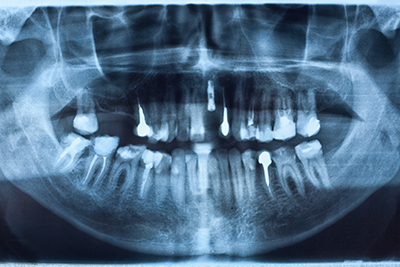

インプラントは、審美的・機能的なメリットはもちろん、周囲の歯に負担をかけない、「お口全体の健康を考えた」治療法です。

当院では数種類のインプラントをご用意しており、患者様の状態によって適宜使い分けを行っております。

例えば、長期間入れ歯を使用していたり、ご高齢で顎の骨が柔らかい方には、「HAインプラント」というものを選択する場合があります。 このインプラントには、表面にハイドロキシアパタイトという生体活性材料がコーティングしてあります。ハイドロキシアパタイトは、だ液中のミネラルイオンに作用して再石灰化を促進する物質です。

これを利用したHAインプラントは、骨が隙間なく生化学的に結合する特性があり、骨が弱い患者様にはピッタリです。

と言いますのは、例えば硬い骨にインプラントを埋め込む場合、先がネジ状になっているインプラントは、しっかりと動かずにねじ込まれます。

でも柔らかい骨の場合、ネジ状部分がゆるくなってしまい、しっかり固定を行えなくなってしまいます。そんな時、骨との隙間を埋めるようにくっついてくれるHAインプラントを使えば、高い確率でインプラントと骨が結合してくれる、という具合です。

このように、しろいファミリー歯科では、患者様の歯の状態に合わせて適したインプラントを使い分け、できる限り負担の少ない治療をめざしております。